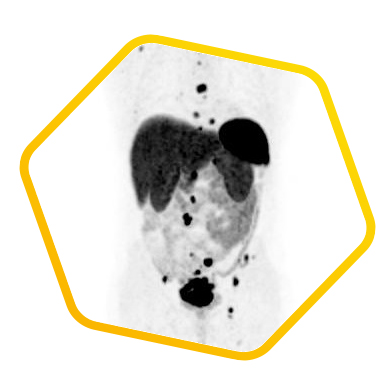

脑神经内分泌肿瘤

双示踪剂PET/CT (F-18 FDG及Ga-68 DOTATATE) 用於评估脑神经内分泌肿瘤体内的扩散情况

![]() [F-18] FDG |

![]() [Ga-68] DOTATATE |